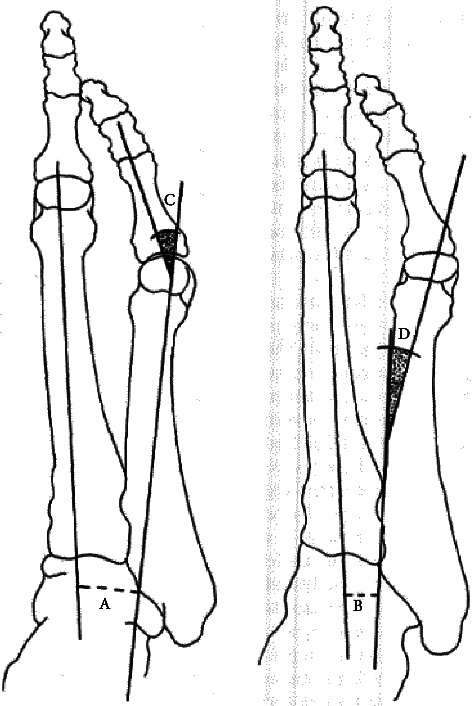

在这篇综述论文中,我们将介绍以下三种常见拇外翻的病因、表现、诊断和治疗方法:足背外翻、足尾外翻和足外翻(HV)。拇外翻是常见的病症,会出现在不同的诊所,因此医疗人员必须对这些病症有基本的了解,才能为患者提供最佳的治疗。许多拇外翻形成的原因多种多样,因此医疗服务提供者可以在需要手术干预之前对其进行处理。本综述旨在引起人们对这些常见拇外翻表现的关注,并扩大对这些表现的认识,以便在早期将发病率降至最低。本综述提供的信息将使初级保健医生和亚专科医生掌握准确诊断和最佳处理这些下肢骨性畸形的知识。

In this review paper, we present the common etiology, presentation, diagnosis, and management of the following three common bunion formations: dorsal bunion, tailor's bunion, and hallux valgus (HV). Bunions are common pathologies that present to a variety of clinics, so it is important for providers to have a base understanding of these in order to provide the best care to patients. Many of these bunion formations have a variety of causes which allow providers to manage them before surgical intervention is required. The aim of this review paper is to bring attention and expanded insight on these common bunion presentations in order to minimize morbidity early on. The information provided in this review will allow both primary care and subspecialty physicians with the knowledge to accurately diagnose and optimally manage these bony deformities of the lower extremity.